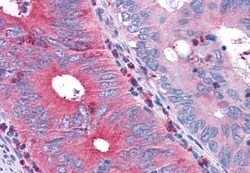

Invitrogen™ TAS1R1 Polyclonal Antibody

| Immunohistochemistry (Paraffin) | |

| Synthetic 16 amino acid peptide from 3rd cytoplasmic domain of human TAS1R1. | |

| Human, Canine, Bovine, Pig, Horse | |